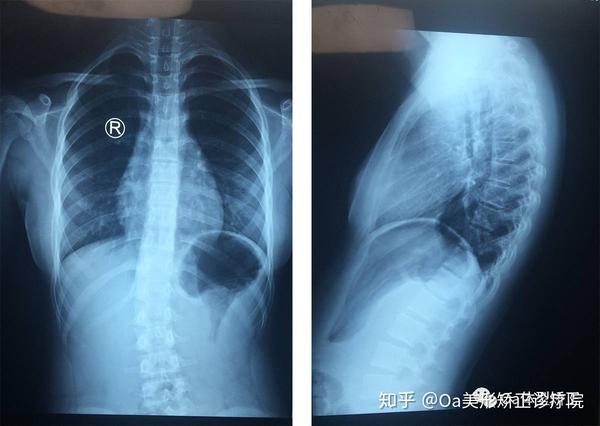

脊柱侧弯x光图片

脊柱侧弯x光图片,轻度脊柱侧弯图片

脊柱侧弯x光图片 x片

轻度脊柱侧弯x光图片

脊柱侧弯图片